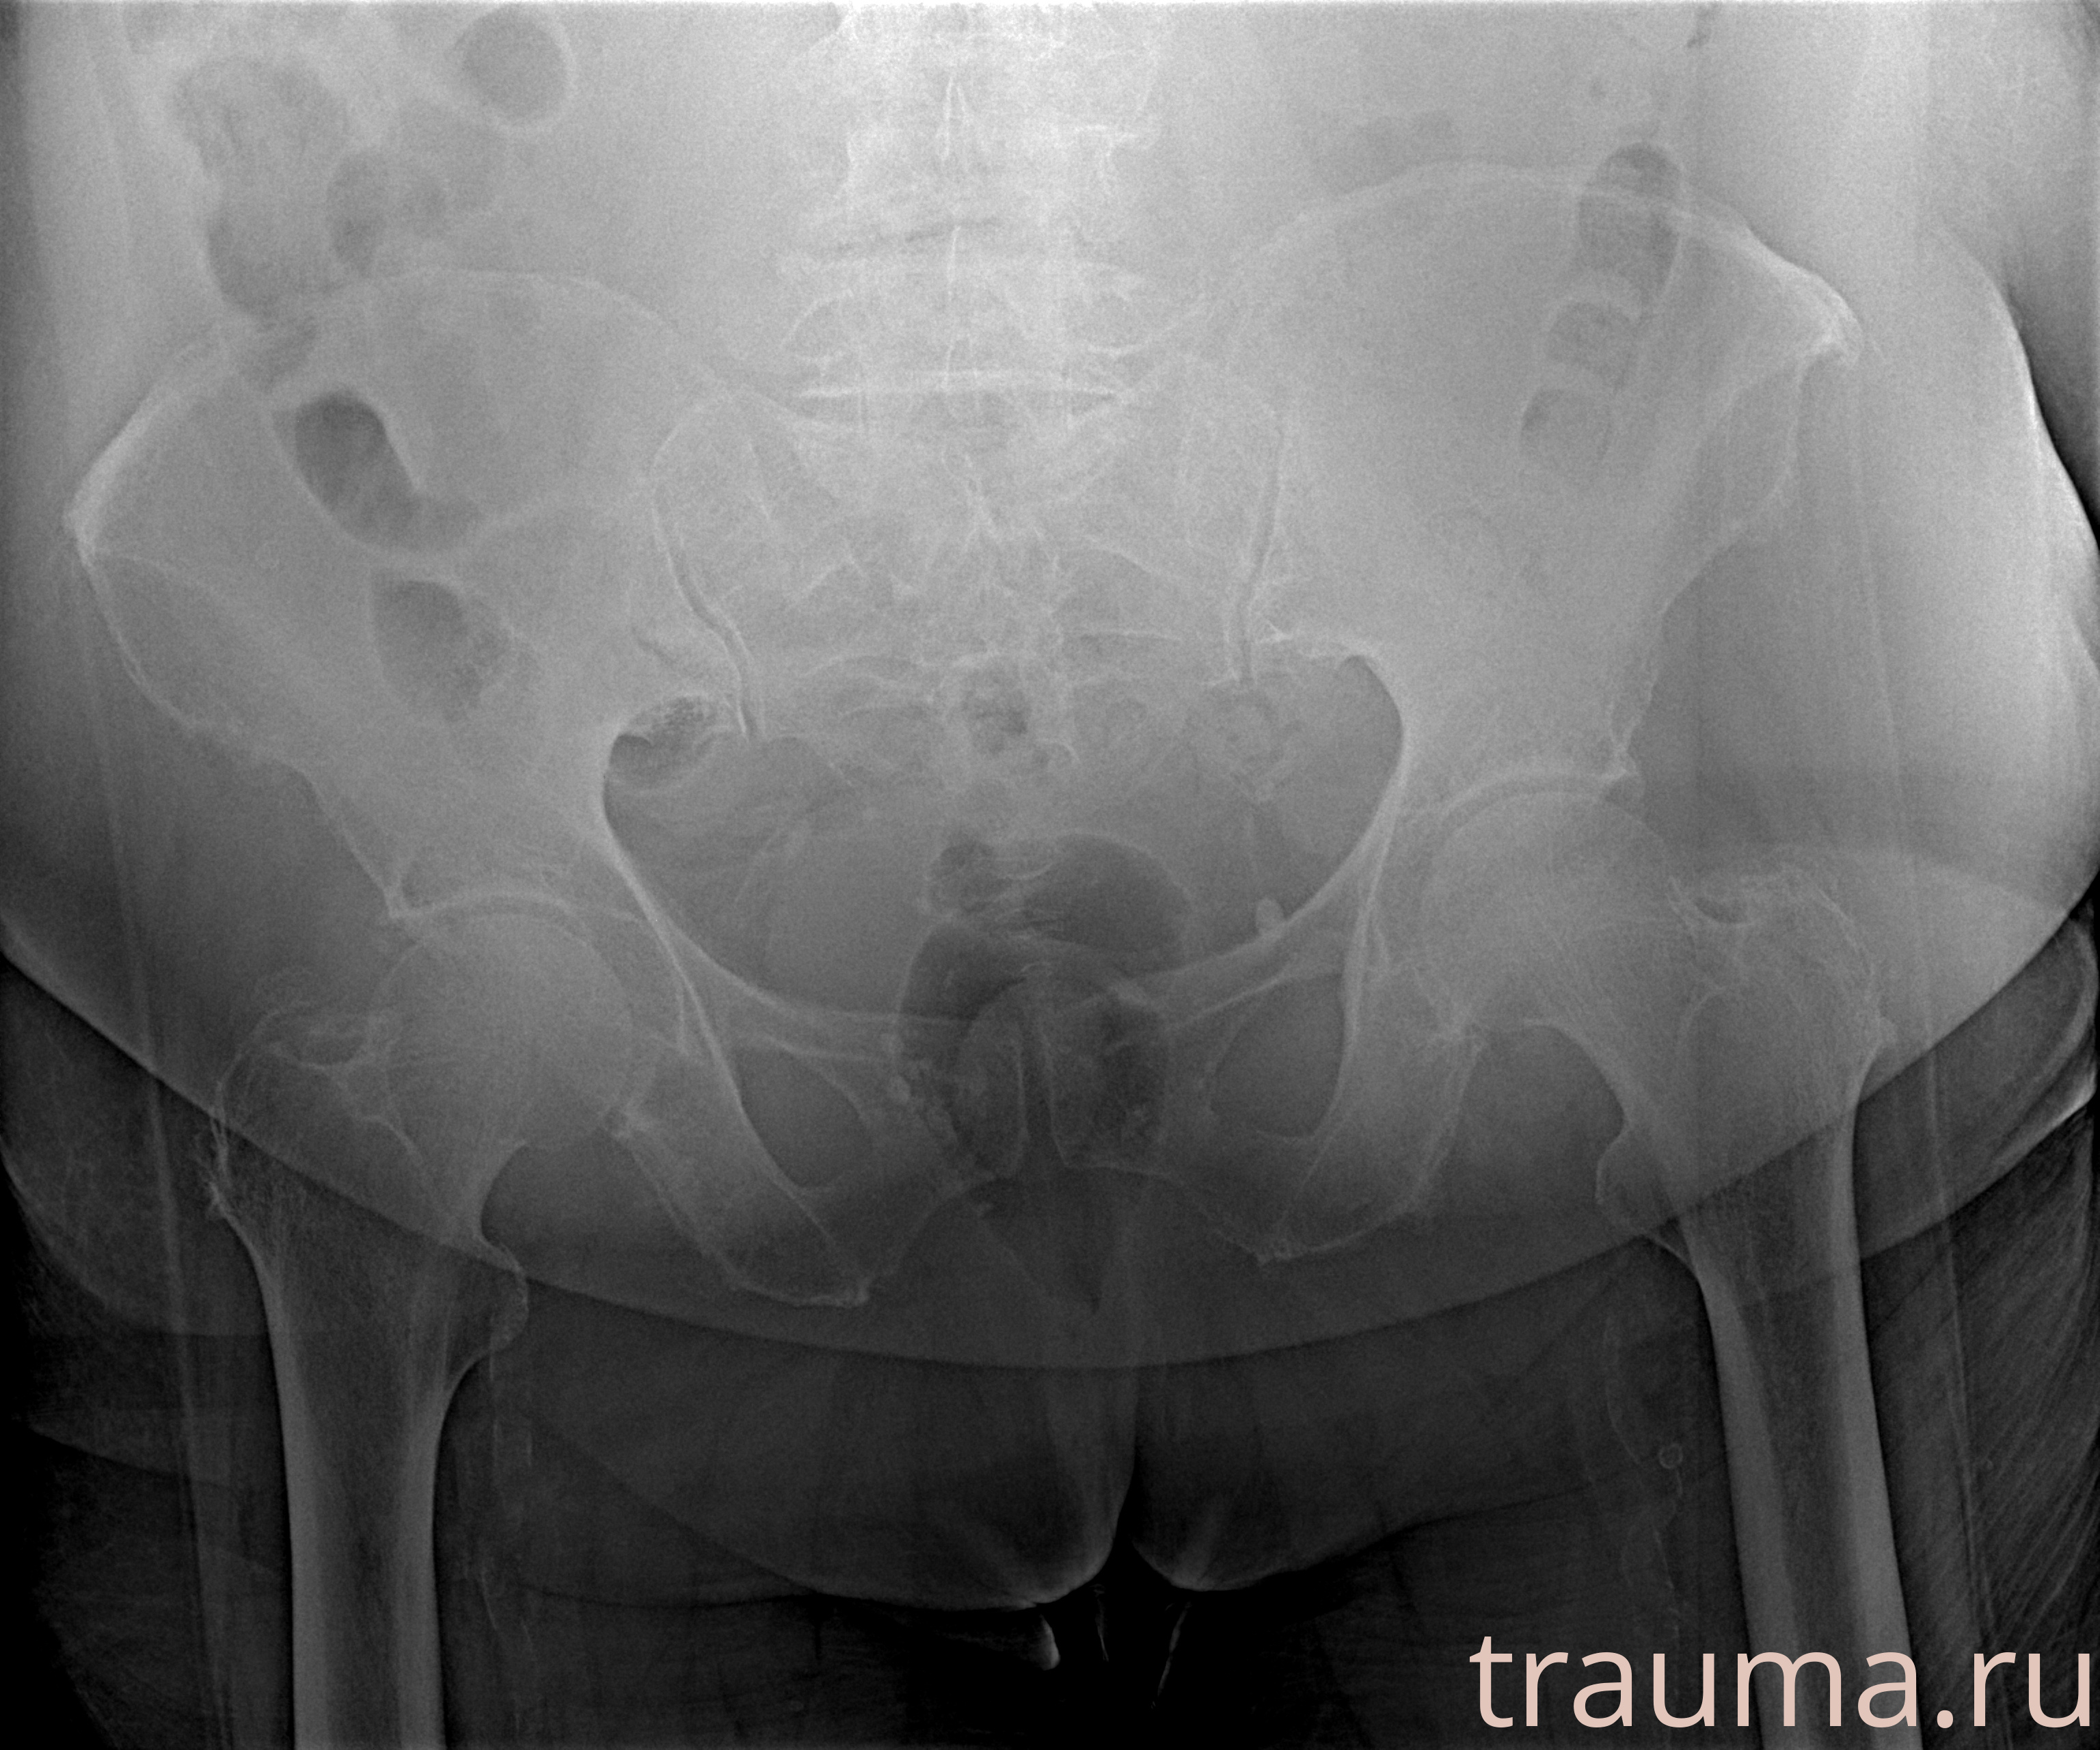

Рентген на дому: по вашему адресу приезжает врач-рентгенолог, травматолог-ортопед с мобильным рентгеновским аппаратом, проводит диагностику травмы или заболевания, делает необходимые рентгенограммы, дает рекомендации по дальнейшему лечению. Получить качественные снимки в домашних условиях возможно благодаря уникальной методике, разработанной МосРентген Центром для института  Склифосовского